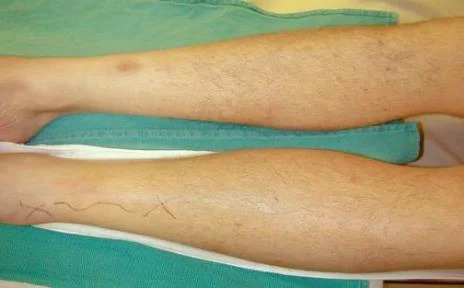

Clinical Picture - Move

- Pain on passive stretch

- Passive dorsiflexion of ankle (leg)

- Passive dorsiflexion of wrist (forearm)

Fasciotomy Principles Continued

- No skin wound closure

- Bulky dressing with a splint

- V.A.C” dressing (Vacuum Assisted Closure)

- ? “Boot lace” vessel loop closure (gradual)